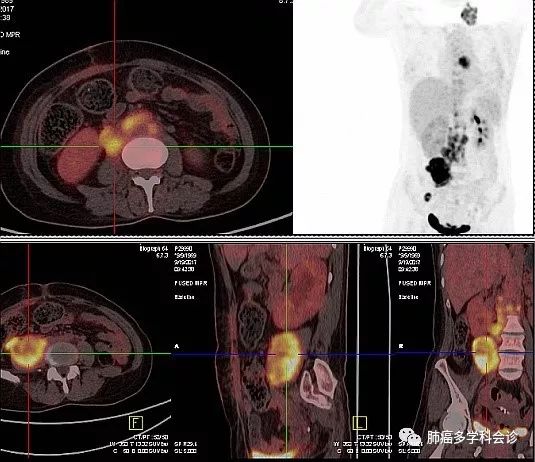

患者始终没有进食不适、梗噎感。经过 2 周期“顺铂+多西他赛”化疗,腹部症状有所缓解,体重增加 2 公斤。2017年11月6日复查 CT ,腹腔转移灶退缩: